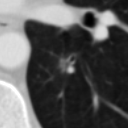

The current study focuses on lung nodule retrieval from a database of CT scans, where patches taken from CT slices of pulmonary nodules are to be mapped into an embedding. LIDC-IDRI [5] is a dataset of thoracic CT scans of 1,010 patients. All the scans were annotated by up to four radiologists, where each one identified, segmented and evaluated separately the lung nodules of a diameter above . Their evaluation also included ratings for a set of 9 characteristics: Subtlety, Internal structure, Calcification, Sphericity, Margin, Lobulation, Spiculation, Texture and Malignancy. The rating system was based on a discrete score of 1-5. Four examples of nodule patches are illustrated in Figure 2: 2 benign (a, b) and 2 malignant (c, d). A rounded vector of the mean rating is bellow each nodule, with the characteristics ordered according to the listing above. The most prominent difference between a and b is the calcification: 3 (solid) and 6 (absent) accordingly. d compared to c has a more defined margin, is more lobulated, but less spiculated. The malignancy score is used to define malignancy classes: score of 1-2 is benign, score of 3 is unknown, and a score of 4-5 is malignant.

(a) Benign

3, 1, 3, 3, 4, 3, 1, 5, 1

(b) Benign

3, 1, 6, 5, 5, 1, 1, 5, 2

(c) Malignant

5, 1, 6, 3, 3, 4, 1, 5, 5

(d) Malignant

4, 1, 6, 3, 4, 2, 2, 5, 4